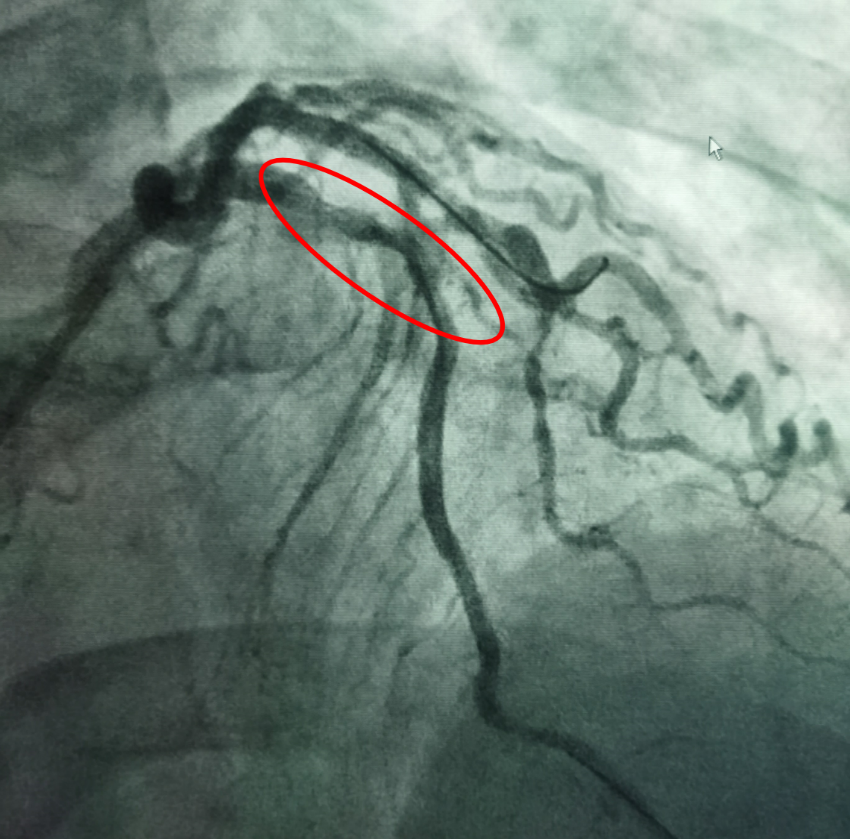

患者吴先生,68岁,有吸烟史20年,高血压史20年,持续胸闷1年,1月前剧烈活动后出现胸闷,持续数小时可自行缓解,入院后诊断为不稳定型心绞痛。冠脉造影显示冠脉左前降支开口可见50%狭窄,近端可见95%偏心狭窄,局部瘤样扩张,可见钙化影(图1),此种情况极易造成支架膨胀不全。据此杨清教授和徐绍鹏教授果断选择3.0 x 12mm Shockwave IVL冲击波球囊对近段钙化病变进行4个周期40个脉冲的预处理(图2),而后植入支架,达到了理想的支架膨胀结果(见图3)。

图1 患者冠脉造影图像:红色弧线区域血管可见明显钙化影(未应用造影剂X线下即可见血管轮廓)